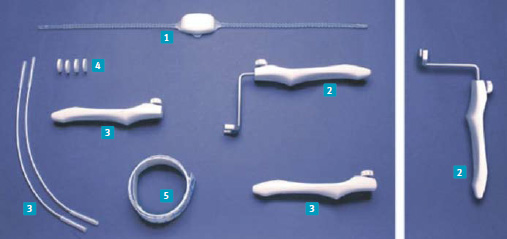

Souhrn / Argus sling je miniinvazivní slingová technika léčby mužské inkontinence. Principem této metody je měkká komprese bulbární uretry silikonovým polštář kem, který je zavěšen z obou stran na vrapovaném silikonovém závěsu, ten je protažen z každé strany pomocí speciálních protahovacích jehel (součást setu) nad sponou stydkou do stěny břišní, kde je zakotven a fixován silikonovými kroužky.

Summary/ Argus sling technique is minimally invasive technique available for the male incontinence treatment. The principle of the implantation method is soft bulbar urethral compression with silicone pad, which is suspended from the both sides of the silicon corrugated hinge that is pulled from each side using special stretching needles (part of set) above the pubic symphysis to the abdominal wall, where it is anchored and fixed with silicone rings.

2 – Utahováky

3 – Protahovací jehly

4 – Silikonové kroužky

5 – Meřítko